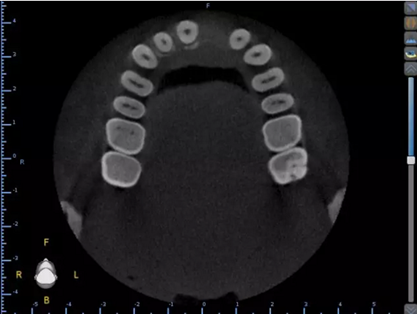

1.術(shù)前CT

2.術(shù)前植體設(shè)計(jì)

3.術(shù)前導(dǎo)板設(shè)計(jì)

頜面部消毒→鋪襟→局麻下翻瓣→帶入導(dǎo)板→定位鉆定位→擴(kuò)孔鉆擴(kuò)孔→植入3.0x13植體→覆蓋螺絲→縫合→沖洗→術(shù)后醫(yī)囑

術(shù)后CT